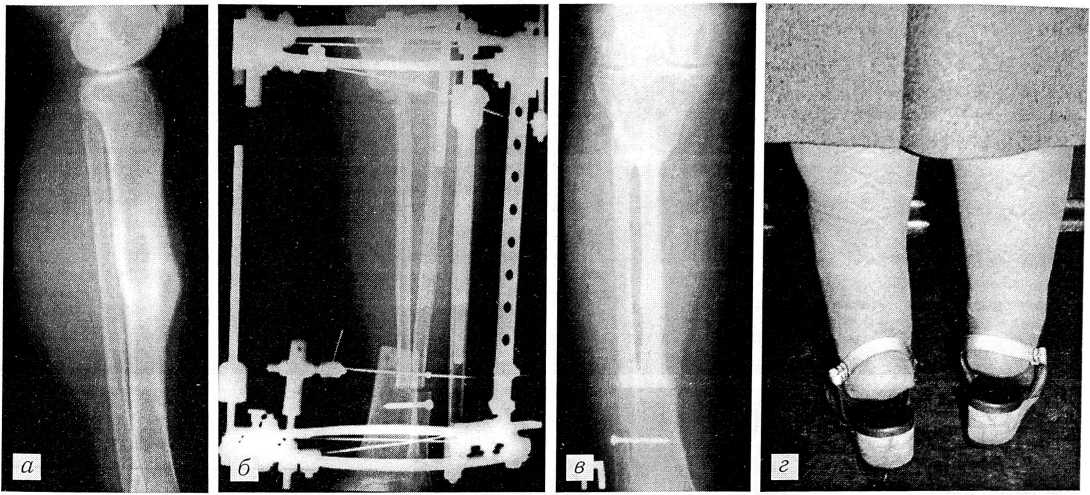

У больной Д., 58 лет, через 4 мес после комбинированного лечения по поводу рака тела матки выявлен солитарный метастаз в диафизе большеберцовой кости справа (рис. 2, а). После курса предоперационной лучевой терапии (общая доза 28 гр) произведена резекция диафиза большеберцовой кости с одномоментным восполнением дефекта (20 см) двумя фрагментами из обеих малоберцовых костей: фрагмент с контралатеральной голени пересажен на микрососудистых анастомозах, с ипсилатеральной — смещен на сосудистой ножке. Наложен аппарат наружной костной фиксации Илизарова (рис. 2, б). Аппарат удален через 4 мес, после полного сращения костных фрагментов. Спустя 3,5 года после операции больная ходит без дополнительных средств опоры (рис. 2, г). Отмечается выраженное утолщение пересаженных фрагментов малоберцовых костей (рис. 2, в). Признаков прогрессирования заболевания нет.

Рис. 2. Больная Д. Солитарный метастаз рака тела матки в диафиз большеберцовой кости справа. а — рентгенограмма правой голени до операции, б — после резекции диафиза большеберцовой кости с восполнением костного дефекта фрагментами контралатеральной малоберцовой кости на микрососудистых анастомозах и ипсилатеральной на сосудистой ножке, в — через 3,5 года после операции (выраженная гипертрофия трансплантатов); г — внешний вид через 3,5 года после операции.